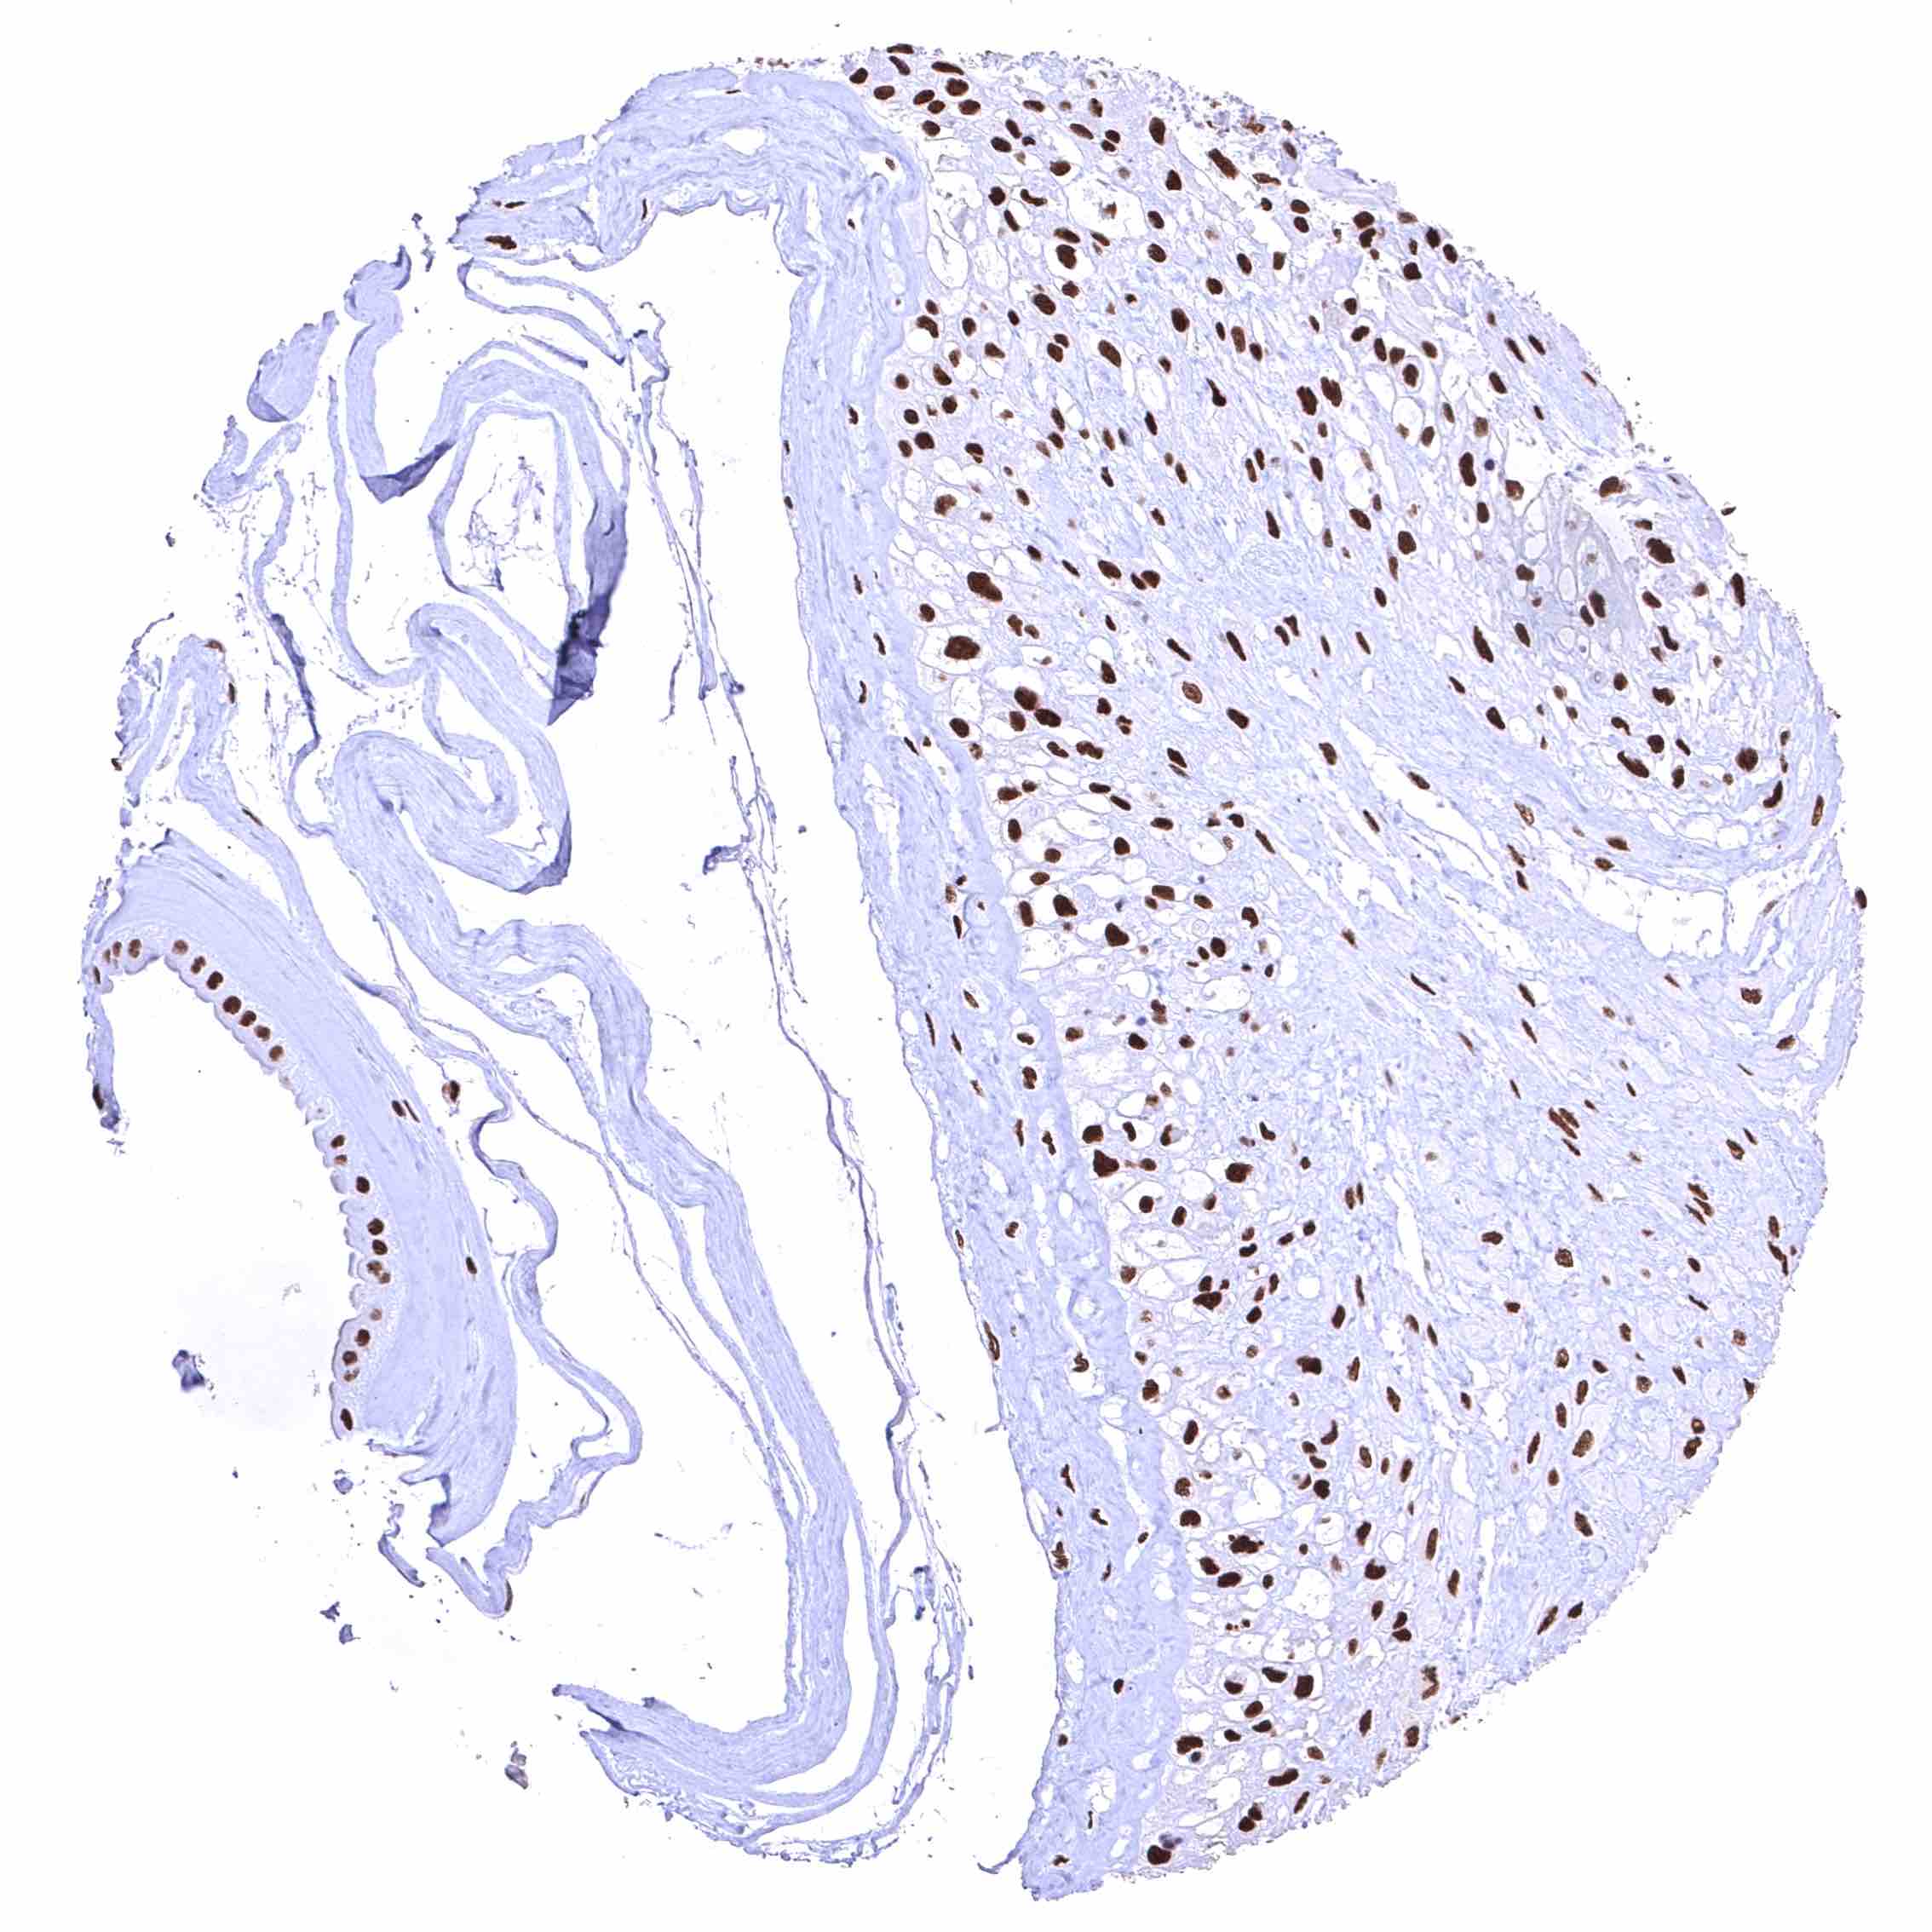

BRD4 antibody [HMV4275] HistoMAX™

Uterus, ectocervix – Distinct nuclear BRD4 staining of squamous epithelial cells with a slight decrease of the staining intensity towards the most superficial cell layers.